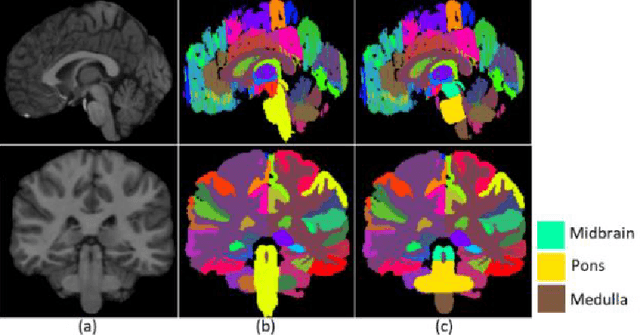

Abstract:About 5-8% of individuals over the age of 60 have dementia. With our ever-aging population this number is likely to increase, making dementia one of the most important threats to public health in the 21st century. Given the phenotypic overlap of individual dementias the diagnosis of dementia is a major clinical challenge, even with current gold standard diagnostic approaches. However, it has been shown that certain dementias show specific structural characteristics in the brain. Progressive supranuclear palsy (PSP) and multiple system atrophy (MSA) are prototypical examples of this phenomenon, as they often present with characteristic brainstem atrophy. More detailed characterization of brain atrophy due to individual diseases is urgently required to select biomarkers and therapeutic targets that are meaningful to each disease. Here we present a joint multi-atlas-segmentation and deep-learning-based segmentation method for fast and robust parcellation of the brainstem into its four sub-structures, i.e., the midbrain, pons, medulla, and superior cerebellar peduncles (SCP), that in turn can provide detailed volumetric information on the brainstem sub-structures affected in PSP and MSA. The method may also benefit other neurodegenerative diseases, such as Parkinson's disease; a condition which is often considered in the differential diagnosis of PSP and MSA. Comparison with state-of-the-art labeling techniques evaluated on ground truth manual segmentations demonstrate that our method is significantly faster than prior methods as well as showing improvement in labeling the brainstem indicating that this strategy may be a viable option to provide a better characterization of the brainstem atrophy seen in PSP and MSA.